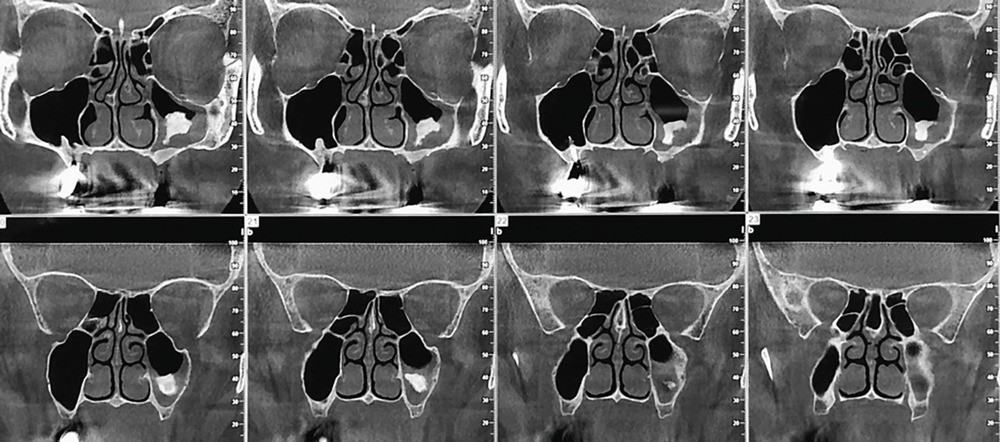

1. CBCT, coupes coronales.

Une patiente âgée de 54 ans, sans antécédent médico-chirurgical, non fumeuse, est adressée par son médecin traitant à la suite de la découverte d’une sinusite maxillaire gauche. Dans la lettre d’accompagnement, il est précisé qu’elle a été opérée à l’étranger, deux mois auparavant, en vue d’une réhabilitation implantaire dentaire. L’interrogatoire révèle qu’une « chirurgie préimplantaire maxillaire postérieure » a été réalisée du fait d’un volume osseux résiduel insuffisant pour réhabiliter l’édentement maxillaire postérieur gauche. Aucun compte rendu opératoire n’est disponible ; la patiente nous informe avoir un rendez-vous pour une chirurgie implantaire dans 4 mois. Nous disposons de l’examen radiographique des sinus maxillaires demandé à la suite de l’apparition d’un mouchage purulent unilatéral associé à des douleurs géniennes homolatérales (fig. 1).

Dans le cas présenté, il s’agit de la découverte tardive d’une migration du substitut osseux dans le sinus maxillaire. Un curetage du sinus maxillaire par la même voie d’abord et sous couverture antibiotique est nécessaire.